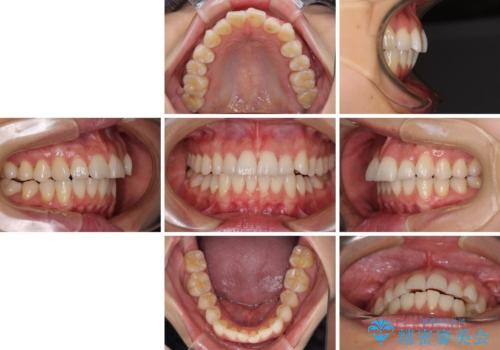

奥歯の咬み合わせは理想的な状態に改善され、その結果として上下歯列もバランスの良い位置に収めることができました。

若干ではあるものの上顎前歯を内側に移動させることができ、以前よりも口が閉じやすいと感じるようになりました。

- 治療期間

- 2年1ヶ月